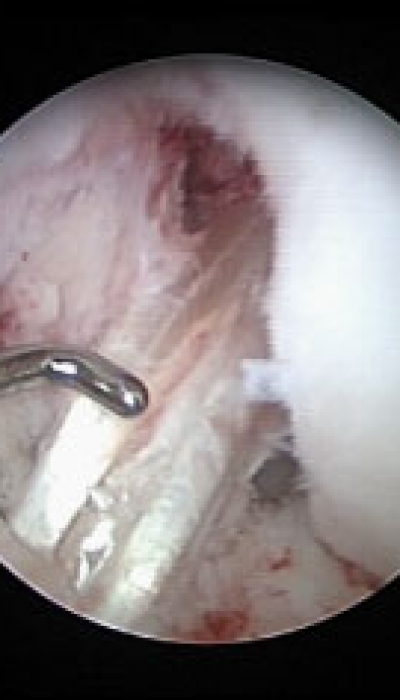

Rodilla